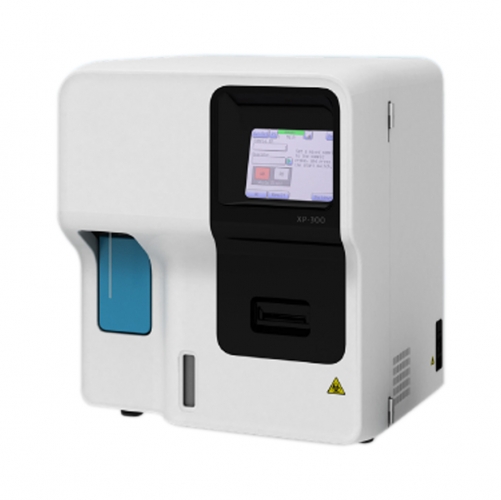

- Hematology Analyzer